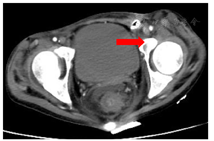

2018年1月,患者左下腹再次破溃流出肠液,再次置入黎氏双套管冲洗引流。腹部CT提示:乙状结肠仍梗阻,肠壁增厚,回盲部炎症狭窄,直肠周围炎(图5,图6)。